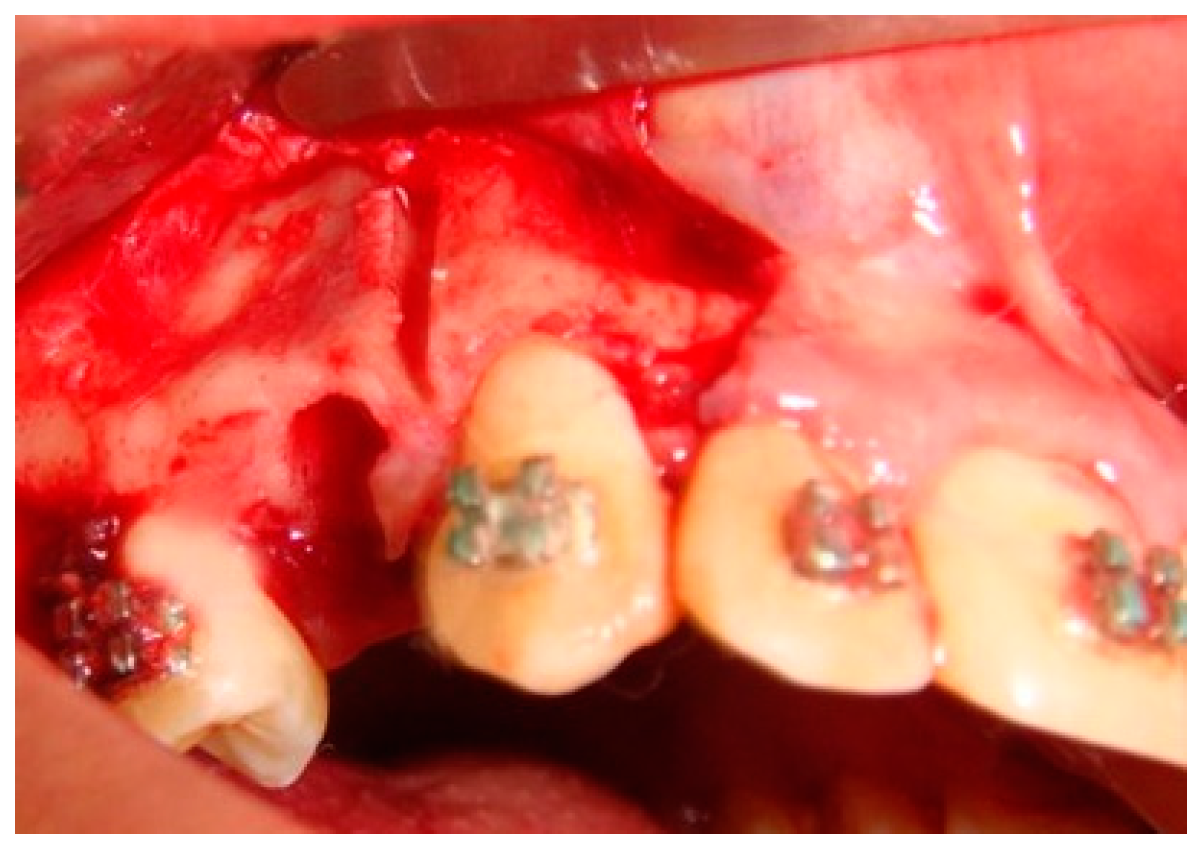

Based on the concept that teeth move faster when the resistance exerted by the surrounding cortical bone is reduced, Köle introduced a surgical procedure involving both osteotomy and corticotomy to accelerate orthodontic tooth movement [17]. Numerous studies have confirmed the usefulness of the corticotomy to accelerate orthodontic tooth movements. However, most of these studies have been conducted on animals [16,17,18,19,20]. A few studies on human subjects have also revealed the merit of this technique [21,22,23]. Therefore, an extensive review of the literature reveals that it is worth exploring the hypothesis that partial buccal corticotomy distal to the canine could enhance canine retraction and avoid the undesirable side effects of canine distraction techniques. Figure 1 offers a representation of clinical image for a better understanding of inside partial corticotomy.

Figure 1.

Surgical site partial corticotomy.